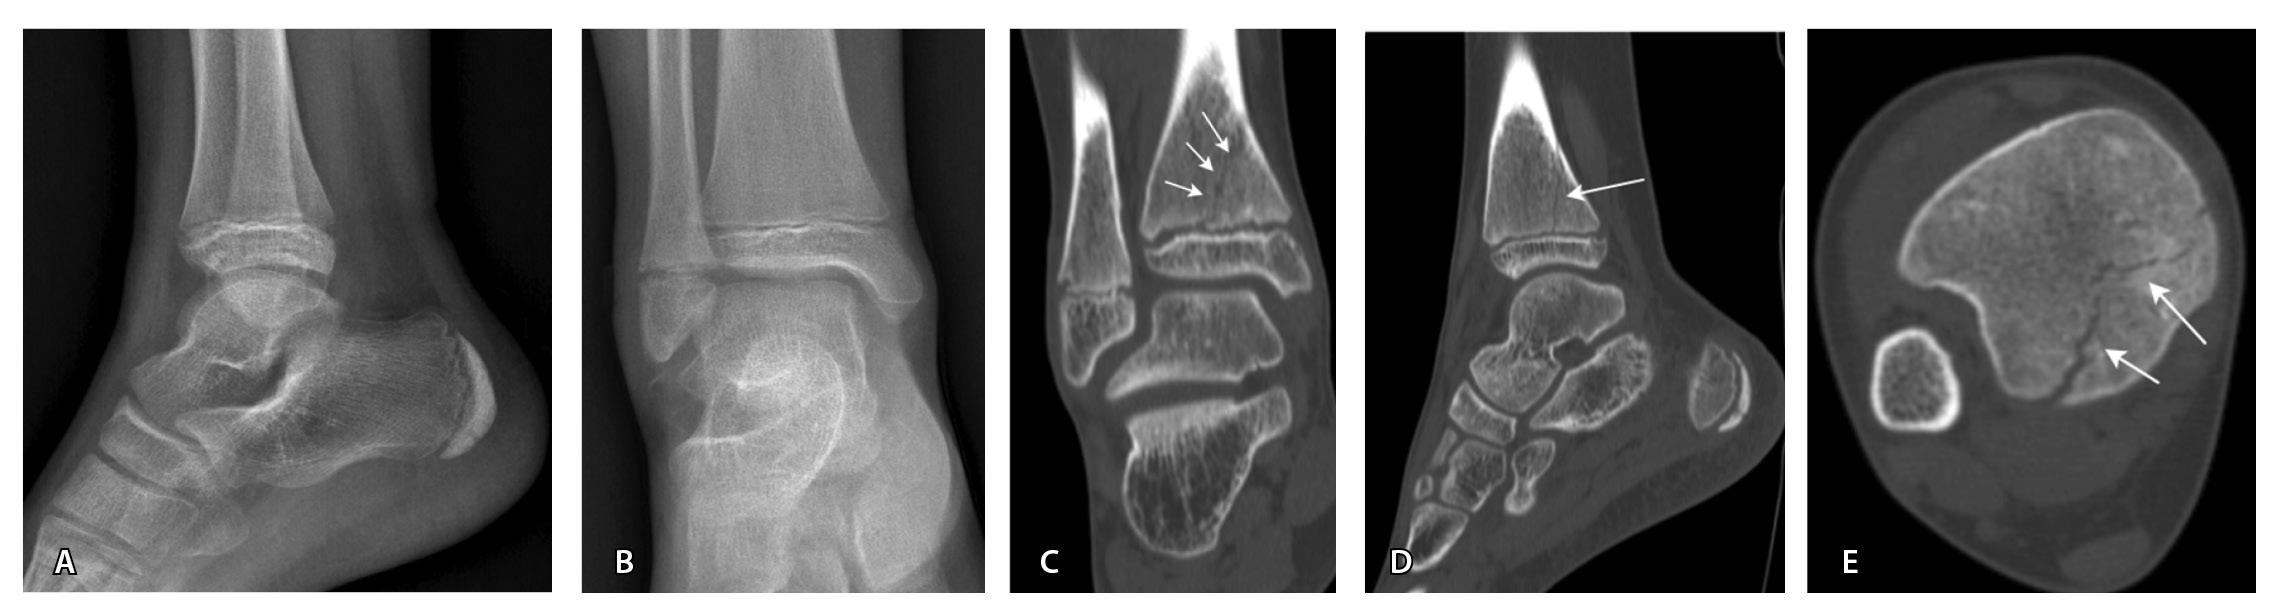

Несмотря на то что МРТ – признанный стандарт диагностики остеохондрального повреждения, КТ также может применяться для определения кортикального повреждения, наличия свободных внутрисуставных костных тел. Кроме того, свободное костно-хрящевое тело маленьких размеров с внутрисуставным смещением не всегда удается визуализировать при МРТ [11, 23, 24, 32]. В проспективном исследовании R.A. Verhagen и соавт. чувствительность и специфичность КТ в диагностике остеохондрального повреждения таранной кости составила 81 и 99% соответственно (МРТ – 96% в обоих случаях) [32].

МРТ – наиболее подходящий метод визуализации остеохондрального повреждения купола таранной кости с чувствительностью и специфичностью 96% [52]. В исследованиях M. Haubro и соавт. [53], M. P. Wilson и соавт. [28] МРТ квалифицирована как золотой стандарт диагностики скрытых переломов по сравнению с КТ и рентгенографией. Протокол, состоящий из корональных T1-взвешенных изображений и STIR, обладает 100% чувствительностью в выявлении рентгеннегативных переломов (рис. 3) [28].

МРТ – первоначальный метод диагностики при подозрении на стрессовые переломы, так как ранним признаком таких переломов служит отек костного мозга пораженной кости, ярко выделяющийся среди остальных неизмененных костей. Отсутствие визуализации костного мозга затрудняет диагностику такого рода повреждений при рентгенографии и КТ (рис. 4). Чувствительность МРТ в выявлении стресс-переломов достигает 99% (95–100%), а специфичность – 97% (88–100%). Несмотря на то что исторически сцинтиграфия была основным методом обнаружения стресс-переломов с почти 100% чувствительностью, в настоящее время выполнение радионуклидного метода не рекомендуется из-за его низкой специфичности и высокой дозы ионизирующего излучения [54].